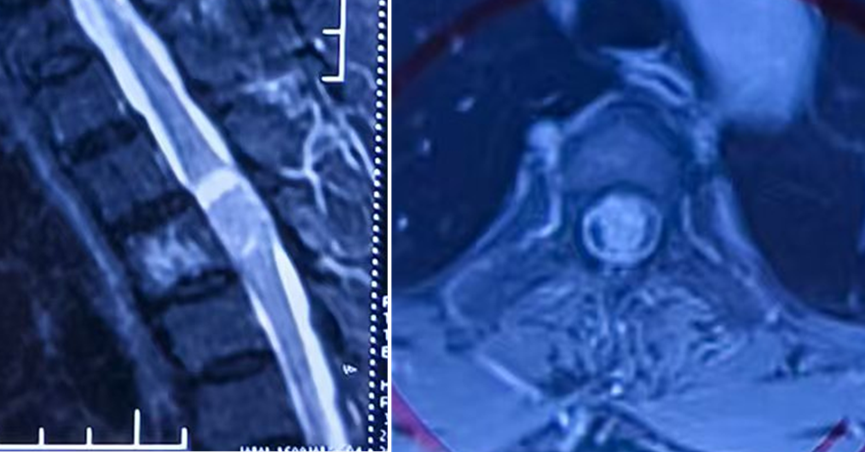

术前胸椎MRI可见椎管内巨大肿瘤,脊髓受压呈线型

术后3天复查胸椎MRI示肿瘤完整切除,脊髓复张良好